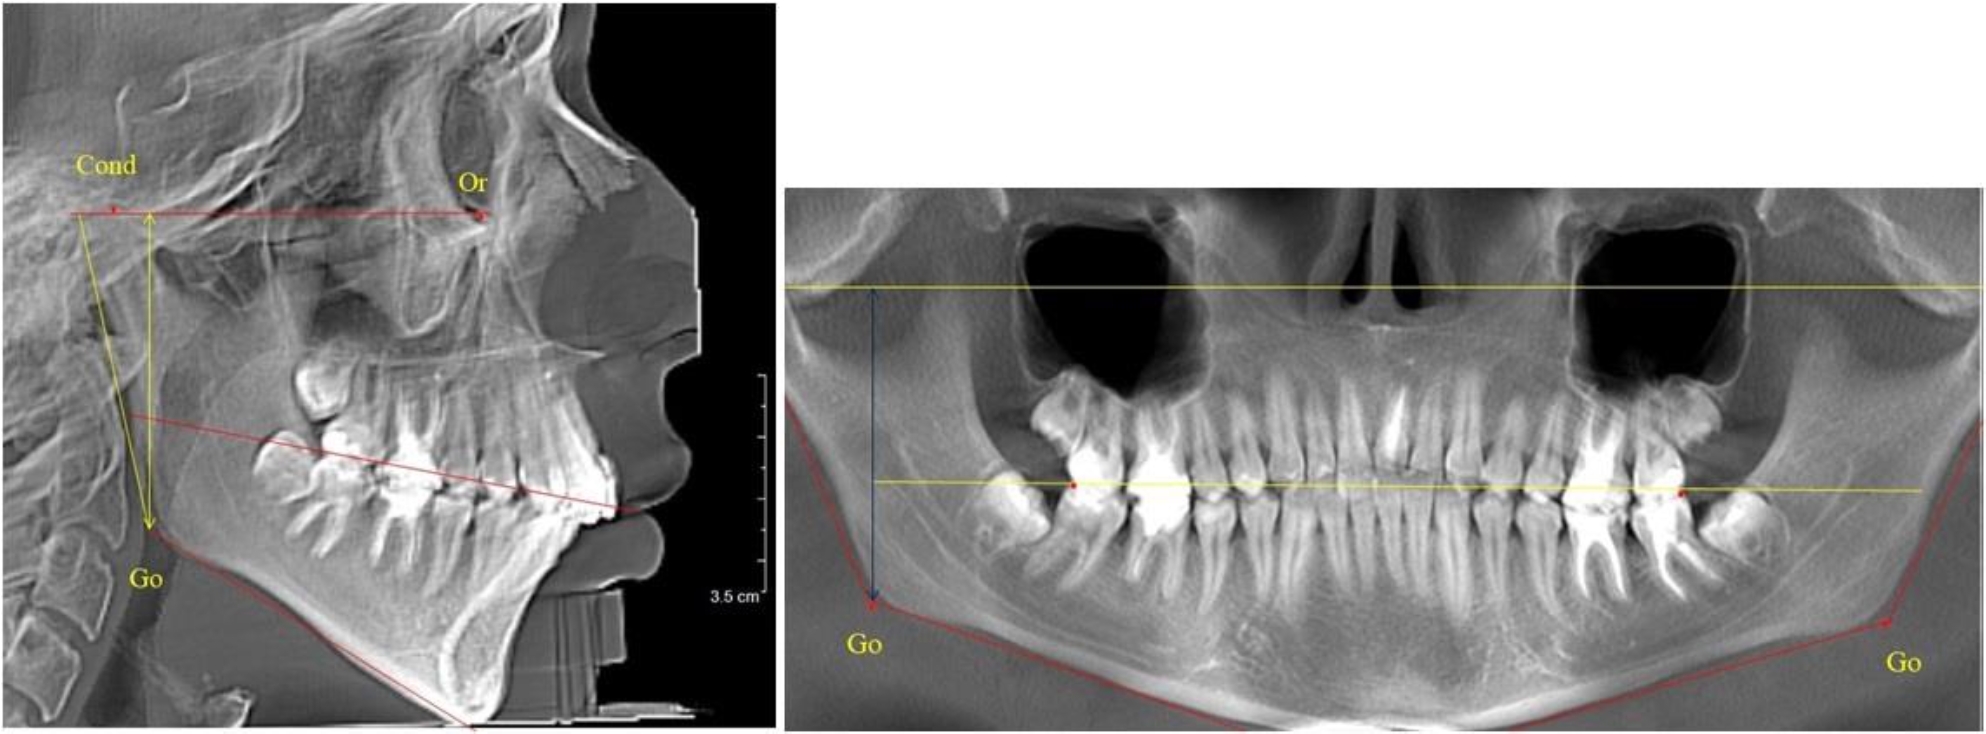

Во 2-й группе были проанализированы 11 телерентгенограмм и 11 ортопантомограмм, что составило (10,38 ± 2,96) % от числа изученных рентгенограмм. На всех рентгенограммах первые постоянные моляры были установлены в окклюзии, и произошла смена нижних медиальных резцов.

На всех парах рентгенограмм угол нижней челюсти, измеренный на телерентгенограмме, так же, как и в 1-й группе, соответствовал углу, полученному при построении угла на ортопантомограмме. Окклюзионная линия делила ветвь на два отдела (рис. 2).

Рис. 2. ТРГ и ОПТГ пациента после прорезывания первых постоянных моляров

Как на ортопантомограмме, так и на телерентгенограмме высота ветви у детей 2-й группы составляла (46,54 ± 2,87) мм, что было несколько больше, чем у детей 1-й группы (р ˂ 0,05). При этом высота верхней окклюзионно-суставной части была (25,42 ± 1,59) мм, а нижней – (21,12 ± 1,77) мм.

Таким образом, верхняя часть была несколько больше нижней, что и определяло рост обеих частей ветви.

Относительные показатели соразмерности частей ветви нижней челюсти показали, что отношение высоты верхней части ветви к нижней в среднем составляло 1,21 ± 0,12. Отношение общей высоты ветви к верхней ее части составляло 1,83 ± 0,13, а отношение общей высоты ветви к нижней ее части было 2,20 ± 0,16, и достоверных различий по относительному показателю отношения всей высоты к верхней и нижней челюсти нами не отмечено (р ˃ 0,05).